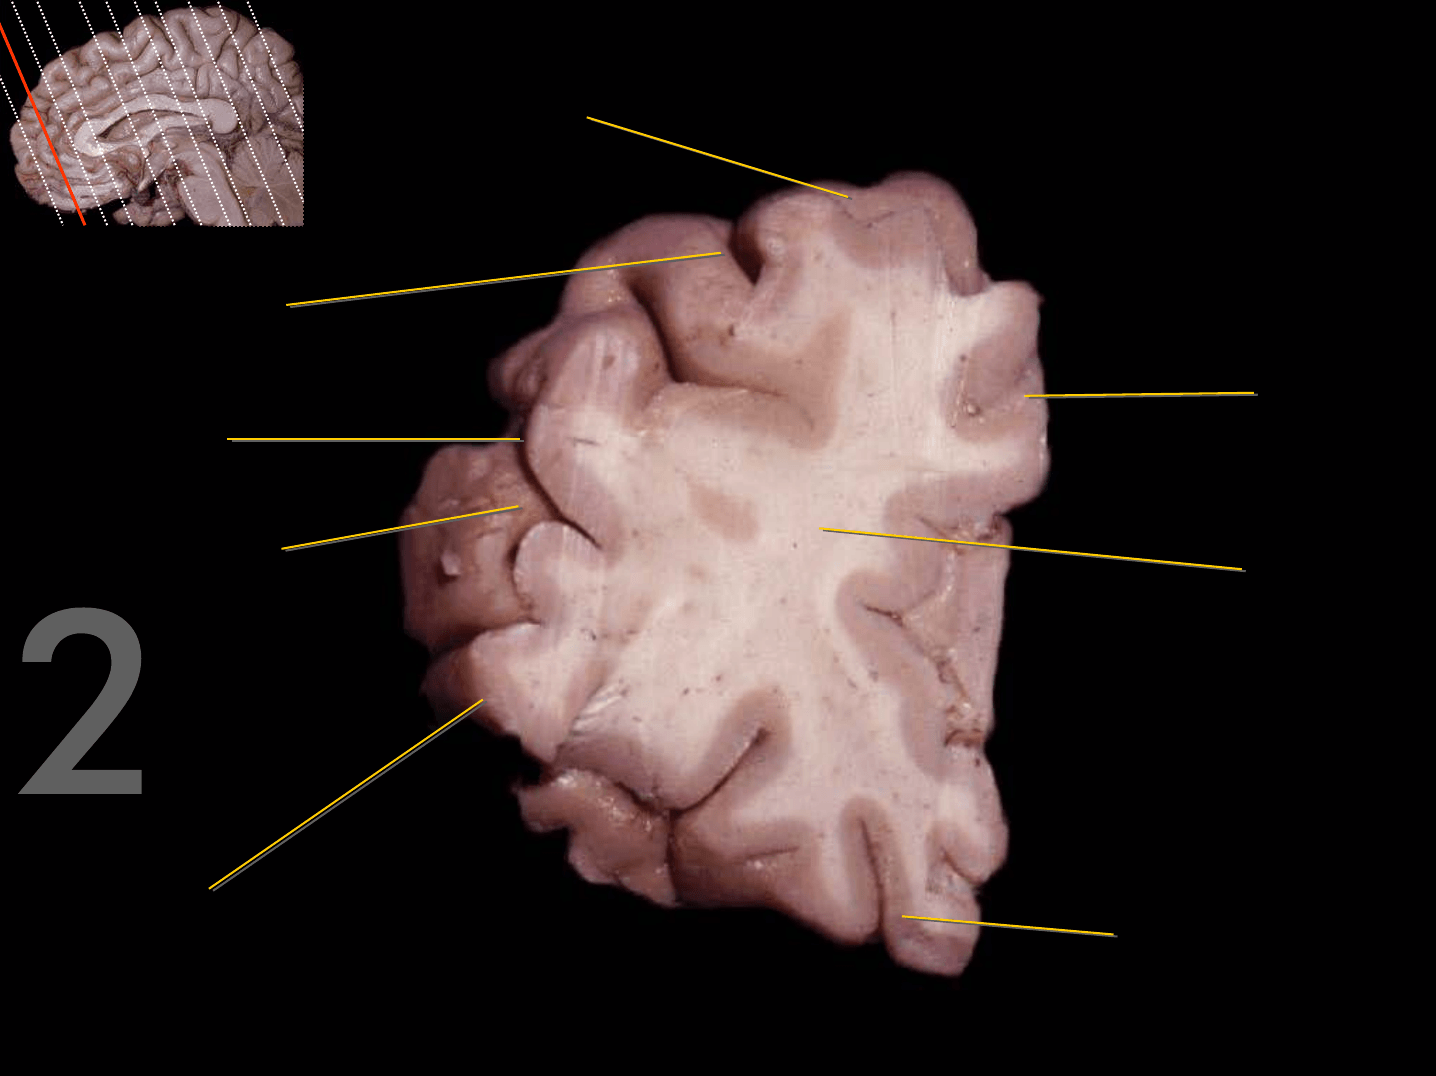

Tronco del cuerpo calloso

Rodilla del cuerpo calloso

Columna del fórnix

Comisura anterior

Foramen interventricular

Infundíbulo

Habénula

Pico del cuerpo calloso

Acueducto del mesencéfalo

Estría medular del tálamo

Adhesión intertalámica

Lámina terminal

Quiasma óptico

Tubérculo mamilar

Comisura posterior

Glándula pineal

Rodete del cuerpo calloso

Calota mesencefálica

Túber cinereum